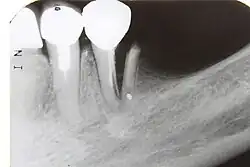

| 7) Root fracture | Mobile or displaced crown segment

Tender tooth that may be bleeding from the gum Tooth may be discoloured (red or grey) |

Fracture line involving the root will be seen as well as the direction | If displaced, reposition tooth and check the position with an x-ray

Flexible splint used to stabilise tooth for at least 4 weeks and then reassess tooth stability Monitor healing for at least 1 year to assess the status of the pulp Root canal treatment will be needed if pulp necrosis develops (this occurs in ~20% of root fractures) |